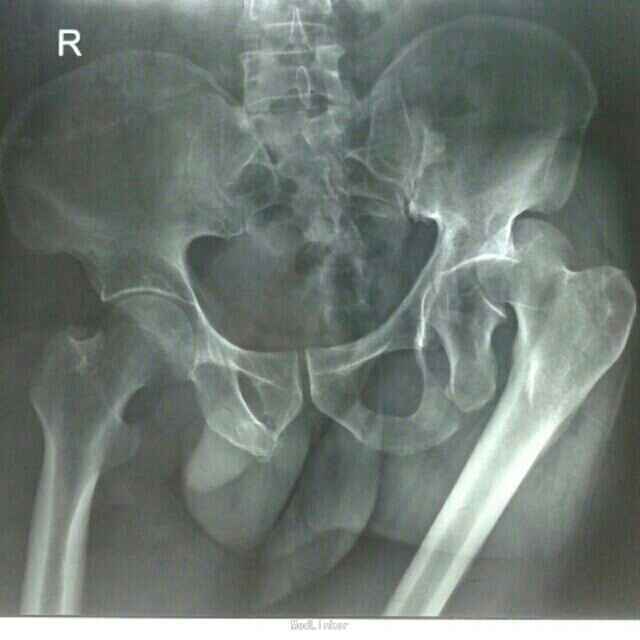

专科检查:双侧髋部、双侧臀部及耻骨部肿胀,压痛明显,伴局部皮下青紫瘀斑,以左侧髋部及耻骨部为甚,可及骨擦感及异常活动;左大腿呈内收、屈曲畸形,左髋关节弹性固定观,骨盆挤压分离试验(+),左下肢纵向叩击痛(+),左髋关节功能活动障碍,右下肢纵向叩击痛(-),左侧髋臼、双侧髂骨部、耻骨部叩击 痛(+),右膝关节前侧可见皮下青紫瘀斑,局部肿胀,压痛明显,未触及骨擦感及异常活动,左膝关节活动轻度受限,被动活动双下肢诉髋臀部疼痛明显;患肢末梢血循、活动及感觉正常。 辅助检查:DR示:左侧髋臼骨折伴左髋关节脱位,双侧耻骨下支、左侧坐骨支骨折,左侧股骨头下骨折可能性大,右侧髋臼骨折可疑。 CT示:左侧髋臼粉碎性骨折,左侧股骨头骨折,左股骨头向上后外侧移位,提示脱位;双侧耻骨支下支、左侧坐骨支骨折,右侧髋臼前份骨皮质稍显皱褶,骨折?左髋关节周围软组织肿胀。 彩超示:腹部未见异常。

诊断:1、重物挤压伤 2、左髋臼骨折合并髋关节后脱位 3、骨盆粉碎性骨折 4、左股骨头骨折 治疗:患者入院后,予以完善术前检查,药物消肿、止痛、止血、补充血容量、保护胃粘膜及预防血栓形成等对症支持治疗,急诊在局部麻醉下行了“左髋关节脱位手法整复+左股骨髁上骨牵引”术,纠正髋关节后脱位及骨折错位畸形, 减轻髋关节压力,降低股骨头坏死的发生几率;经牵引治疗1周后,患者左髋关节弹性固定畸形及左下肢内旋、内收畸形纠正;复查牵引后DR及CT回示:左髋关节脱位已经纠正,骨折错位明显改善,完善相关检查及术前准备在"全身麻醉"下行了"骨盆粉碎性骨折切开复位钢板螺丝钉内固定+同种异体骨植骨+左胫骨结节骨牵引术"。术中见:左侧髋臼顶部及后侧壁骨折,呈粉碎性,后侧骨折线自髋臼上缘3.0cm处向后下走形,连接左侧坐骨支,向外后移位改变,左股骨头向后上脱位不稳,左侧髋臼顶部骨块向外上翻转移位,左髋臼内顶及后壁及股骨头见部分软骨挫伤、凹陷、瘀血,关节腔内见多枚细小骨碎片,关节腔及骨折断端见部分关节囊及软组织嵌顿。术后予患肢继续左下肢胫骨结节骨牵引制动,结合药物静滴预防感染、消肿、止痛、止血、改善血循环等处理,并指导患者行患肢主动功能锻炼;术后2周伤口愈合拆线,住院40天好转出院。